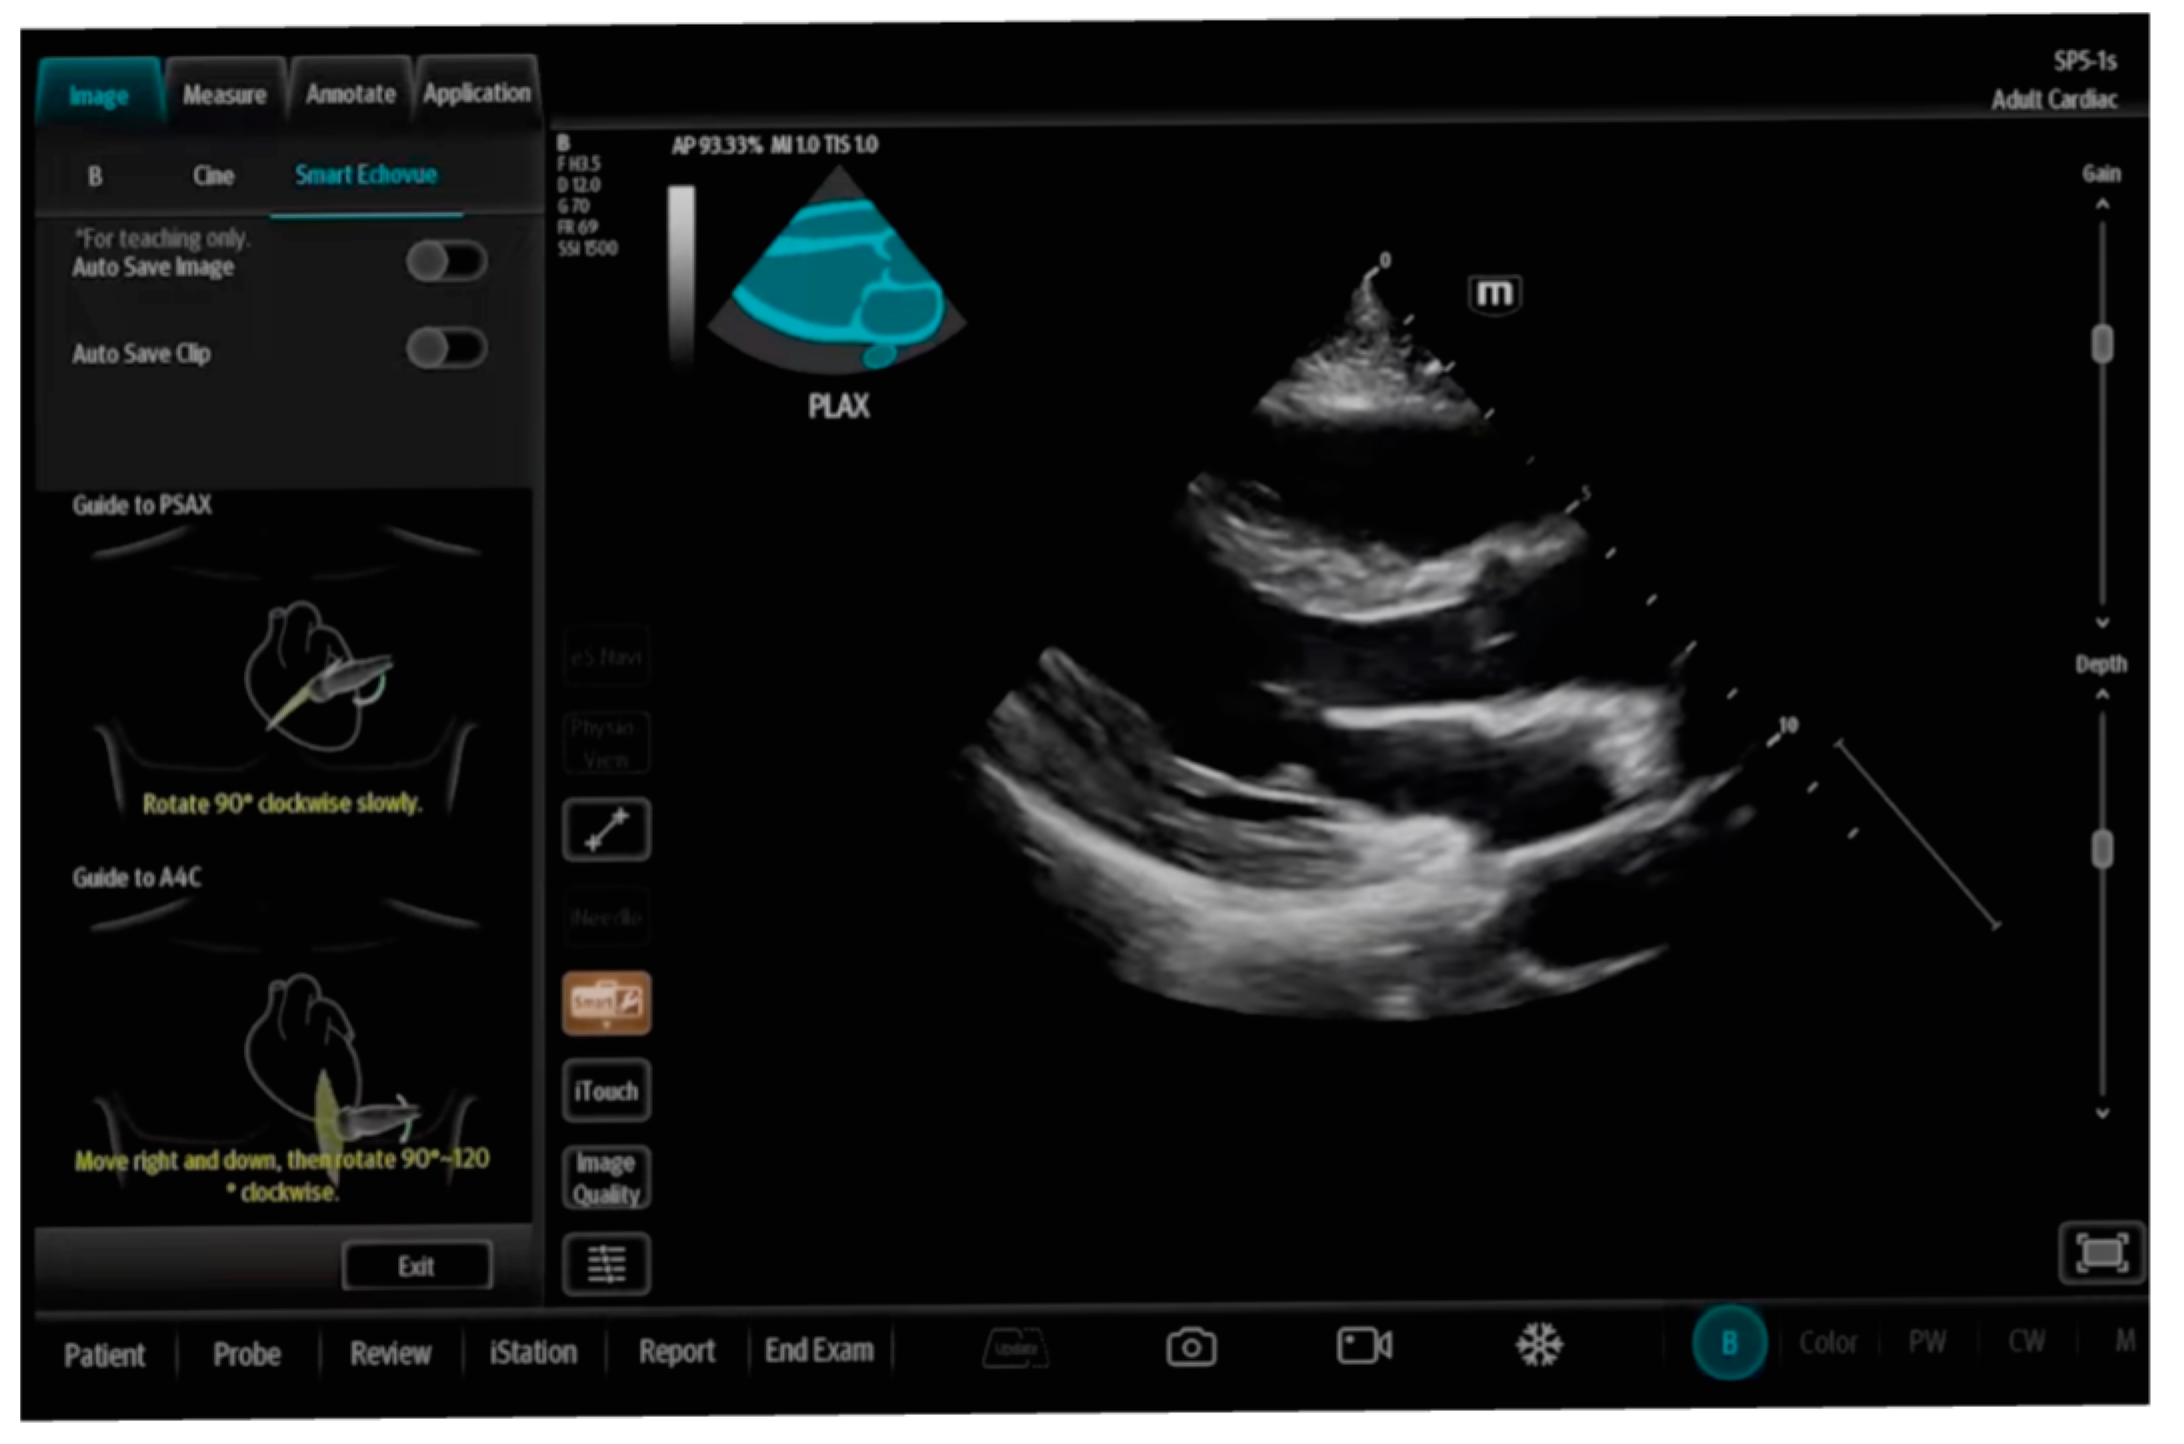

| SmartEchoVue | Mindray | assessment of views | Whole body |

| Us2.ai and AI TRO | EchoNous | ||

| Butterfly ScanLab | Butterfly Network | ||

| LVivo Seamless | Philips | ||